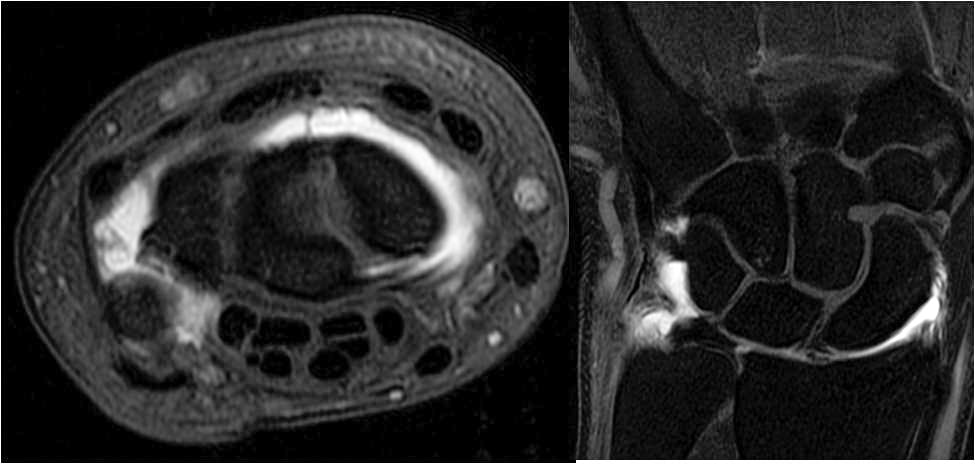

- To train fellows to become efficient, practical, and skilled in the multi-modality imaging of rheumatologic disease and sports related injuries including conventional radiography, CT, arthography, ultrasound and MRI.

- To train fellows to become proficient in orthopedic oncologic imaging including conventional radiography, ultrasound, CT, and MRI.

A wide range of diagnostic services including radiography, US, CT, MRI, and arthrography are complemented by an active MSK interventional service providing diagnostic arthrography, joint injections, and bone and soft tissue biopsies.

The fellows responsibilities include assisting the attending staff in resident education and training. The fellowship focuses on achieving a comprehensive understanding of the basic principles of MSK imaging including MRI and CT imaging protocol optimization for sports medicine, bone and soft tissue neoplasms, rheumatologic disease and arthrography.